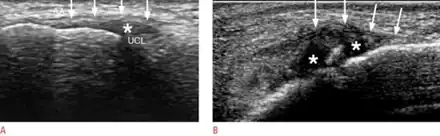

When approaching this type of injury, the physician must first determine whether there is an incomplete rupture (or sprain) of the UCL, or a complete rupture. If the UCL is completely disrupted, the physician must then determine whether there is interposition of the adductor aponeurosis (Stener lesion), or simply a complete rupture of the UCL with anatomic or near-anatomic position. Radiographs are helpful in determining the possible presence of an avulsion fracture of the proximal phalanx insertion site of the ulnar collateral ligament. Stress examination, or one done under fluoroscopic guidance, can help determine the integrity of the ligament.

Most gamekeeper's thumb partial injuries are treated by immobilizing the joint in a thumb spica splint or a modified wrist splint and allowing the ligament to heal. However, near total or total tears of the UCL may require surgery to achieve a satisfactory repair, especially if accompanied by a Stener lesion.